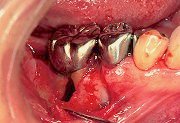

2

| 歯肉弁を剥離したところ、頬側に II級根分岐部病変が認められた。 分岐部内の肉芽を完全に除去し、根面をルートプレーニングし終わった状態。 |